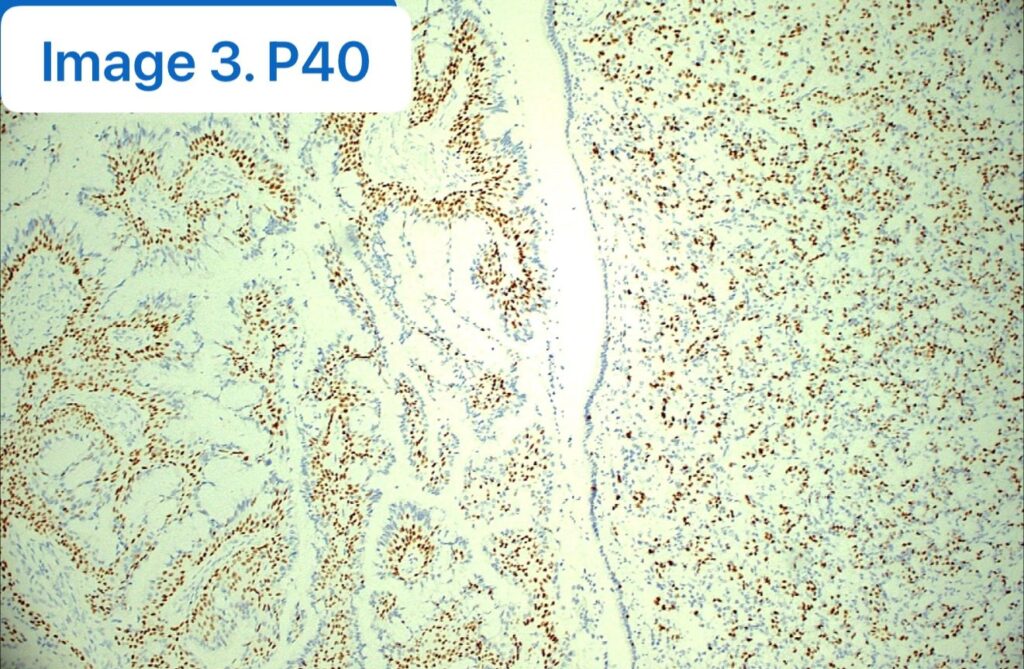

🔬 【免疫组化(IHC)一锤定音】

- P40: 完美勾勒出完整的基底细胞层(图3,良性特征的关键证据)